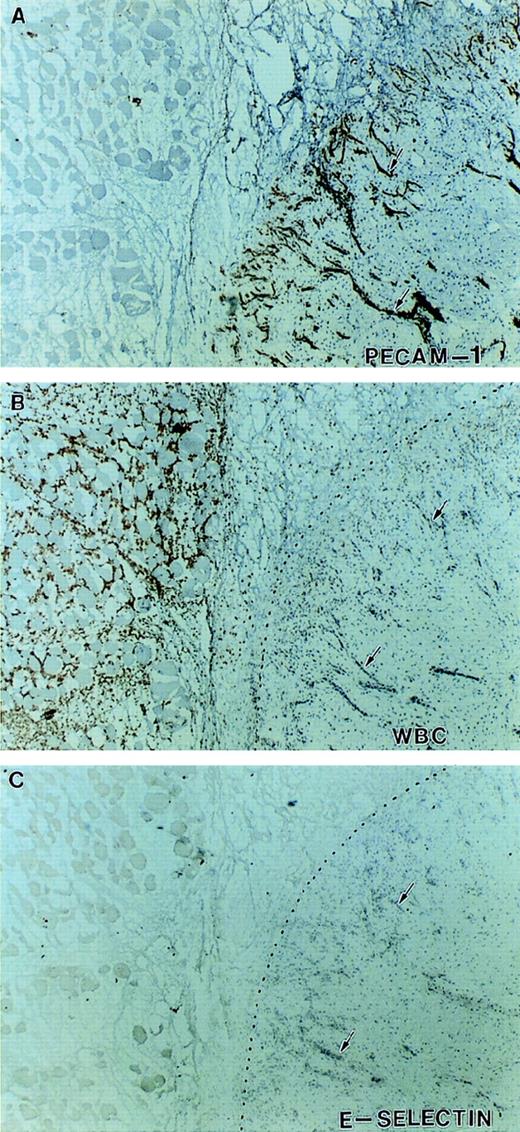

Expression of E-selectin in inflamed tissue. Immunohistochemical staining of serial sections at the junction between viable and necrotic tissue indicated by the dotted line. Sections were stained with antibodies against PECAM-1 (A), Mac-1 (B), and E-selectin (C). There is intense neovascularization at the interface of viable and necrotic tissue (A) and infiltration of Mac-1–positive leukocytes (neutrophils and monocytes) in the necrotic tissue (B). Despite this indication of active inflammation, no significant expression of E-selectin was detected on any of the vessels in this tissue (arrows).

After the patient’s amputation (see Patient history), tissue from the necrotic muscle flap, the nonhealing ulcer and the surgical margin were obtained and processed for immunohistochemical staining. The availability of this tissue provided the opportunity to evaluate the expression of cell adhesion molecules on the endothelium of her vasculature known to be involved in leukocyte recruitment. Immunohistochemical staining of multiple (>6) tissue sections from three distinct sites were performed. The margins of the ulcer showed that although PECAM-1, ICAM-1, and P-selectin were expressed on the vasculature, no expression of E-selectin was detectable on the vessels (large or small) from inflamed tissue (Figs 6 and7). Staining with 3 different anti–E-selectin antibodies gave similar results. There was also patchy staining for VCAM-1 on her endothelium (data not shown). Figure 8 shows serial sections of tissue from the junction between necrotic and viable tissue. In this obviously inflamed tissue, as evidenced by the presence of Mac-1 positive leukocytes (neutrophils and monocytes) and intense neovascularization, no expression of E-selectin was noted on the vasculature. In contrast, staining of tissue from the margins of chronically infected nonhealing wounds/ulcers located on the lower extremities of 2 diabetics who were at risk for amputation showed the expression of E-selectin on vessels in these tissues (Fig9). Of note, although our patient appeared clinically to manifest less pus formation, the presence of extravascular leukocytes as indicated in Fig 7, suggests that her leukocytes still had some capacity to migrate into sites of infection or injury.

An important question is how might the loss of the endothelial surface expression of E-selectin with an accompanying increase in circulating sE-selectin increase the susceptibility to infection in this patient? There are a number of possibilities. First, given the role of selectins in the initial rolling phenomena, the loss of endothelial surface expression of E-selectin may compromise the ability of leukocytes to roll along the endothelium and therefore impair leukocyte emigration into sites of inflammation. However, mutant mice deficient in E-selectin do not show an increased incidence of spontaneous infections, and neutrophil recruitment in response chemical-induced peritonitis is impaired only if P-selectin is also simultaneously blocked.26 These and other studies with selectin-deficient mice27 28 suggest that with respect to the process of leukocyte recruitment, E- and P-selectin may serve redundant functions, and/or that in the setting of chronic loss each may be able to compensate for the persistent absence of the other. Consistent with this proposal is the demonstration in our patient of P-selectin endothelial expression and some extravascular accumulation of Mac-1–positive leukocytes in chronically inflamed tissues (Fig 8). While data from mutant mice are very instructive, its is possible (and probably likely) that the specific or relative functions of P- and E-selectin in humans differ from that of mice, and therefore care should be exercised in extrapolating from the murine studies.